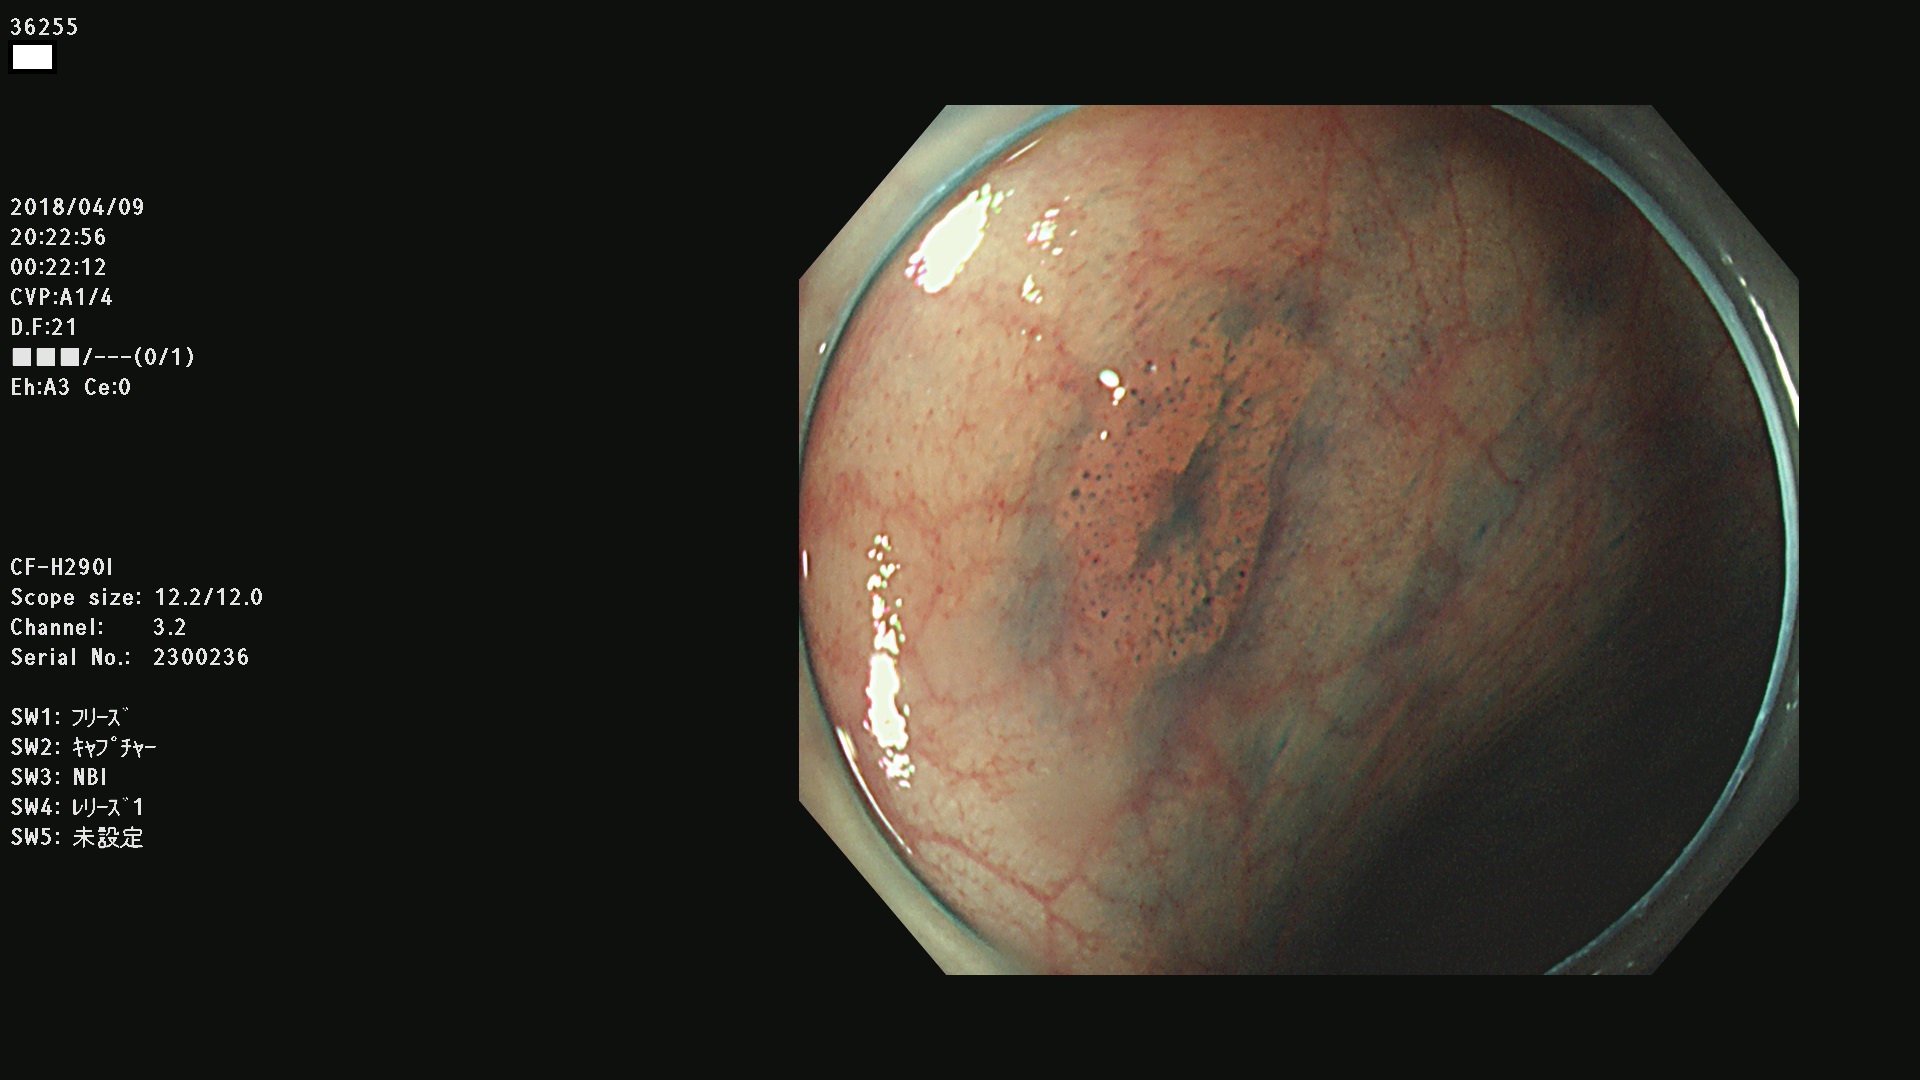

36201 36202 36203 36205 36207 36209 36210 36212 36213 36214 36215 36217 36220 36221 36222 36224 36225 36226 36227 36229 36230 36231 36232 36235 36236 36238 36240 36243 36244 36246 36247(SSAPのみ。SPS) 36248 36249 36251 36252 36253 36254 36255 36256 36257 36258 36259 36261 36262 36264 36265 36267 36269 36270 36272 36274 36275 36276 36279 36280 36281 36283 36285 36288 36289 36291 36292 36295 36296 36297 36299

発見困難で危険性の高い平坦型病変(上記100名より抽出)